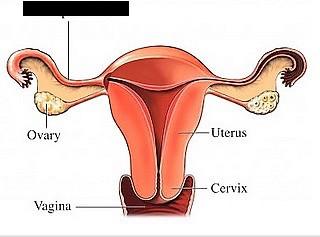

Ovary

Uterus

Cervix

Vagina

Uterine (=fallopian) tube

Labia majora/minora

Vaginal orifice

Vestibule (of vulva)

Clitoris

Prepuce (=clitoral hood)

Overian ligament

Round ligament (of uterus)

Broad ligament